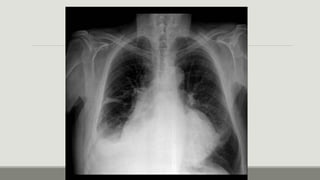

Rx de tórax

Fase

intersticial:

Pérdida de la definición de los vasos

pulmonares, engrosamiento de los

tabiques interlobulillares (líneas A y B de

Kerley), nódulos acinares perhiliares,

manguitos peribronquiales,

engrosamiento de las cisuras.

Rx de tórax Fase intersticial: Pérdidade la definición de los vasos pulmonares, engrosamiento de los tabiques interlobulillares (líneas A y B de Kerley), nódulos acinares perhiliares, manguitos peribronquiales, engrosamiento de las cisuras.